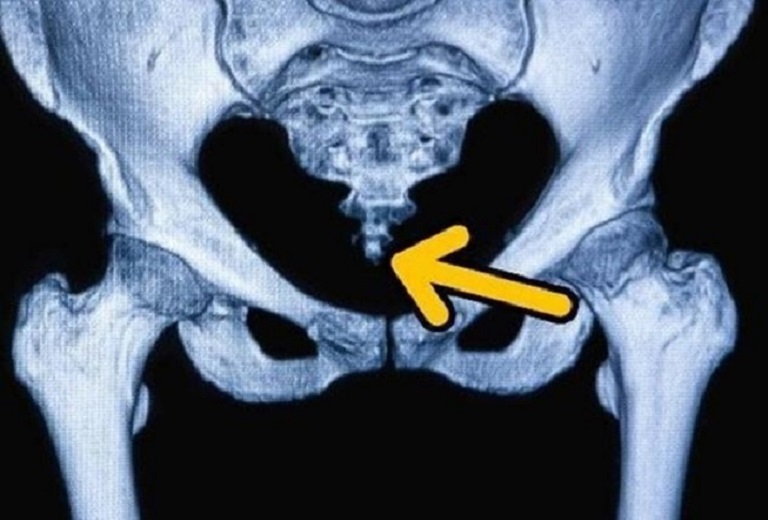

Đau xương cụt (Coccydynia hoặc Tailbone Pain) xảy ra do xương cụt bị mất ổn định dẫn đến viêm các khớp lân cận (đặc biệt là khớp cùng chậu). Cơn đau ở xương cụt sẽ chuyển biến từ nhẹ đến dữ dội và thường tăng nặng khi ngồi xuống, đứng lên hoặc ngả người ra sau khi ngồi trên ghế.

2. Nguyên nhân dẫn đến đau xương cụt

Xương cụt bị dị dạng hoặc lệch vị trí bẩm sinh.

Chấn thương khiến xương cụt bị rạn nứt, gãy hoặc lệch khỏi vị trí.